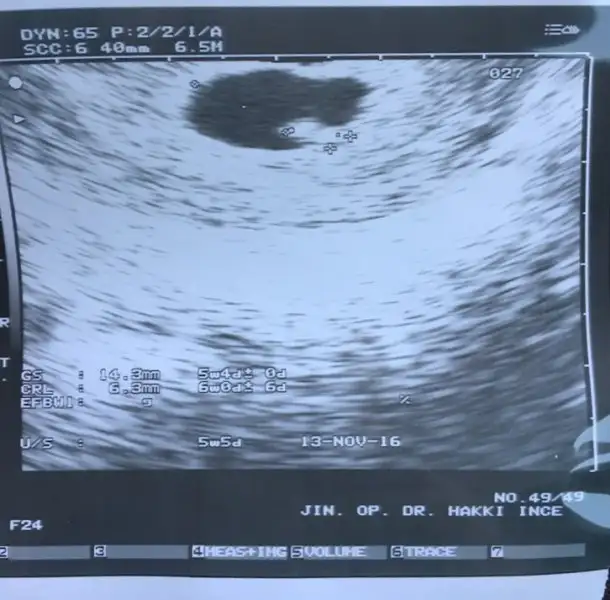

6+7 onemli himm benim ikizler 8+2 di canim yanilmami oluyor6-7 haftalık usg lazim cnm

Cnm en fazla 8 haftaya kadar oluyor,sonrasında bebek her yere geçtiği için yanılma olabiliyor6+7 onemli himm benim ikizler 8+2 di canim yanilmami oluyor

himm o zaman yanildik insllah :) ikizlerim kizdir hissediyorum ilk gunden bu yana hep kiz dedim rabbim nasip eder insallah ... aminCnm en fazla 8 haftaya kadar oluyor,sonrasında bebek her yere geçtiği için yanılma olabiliyor